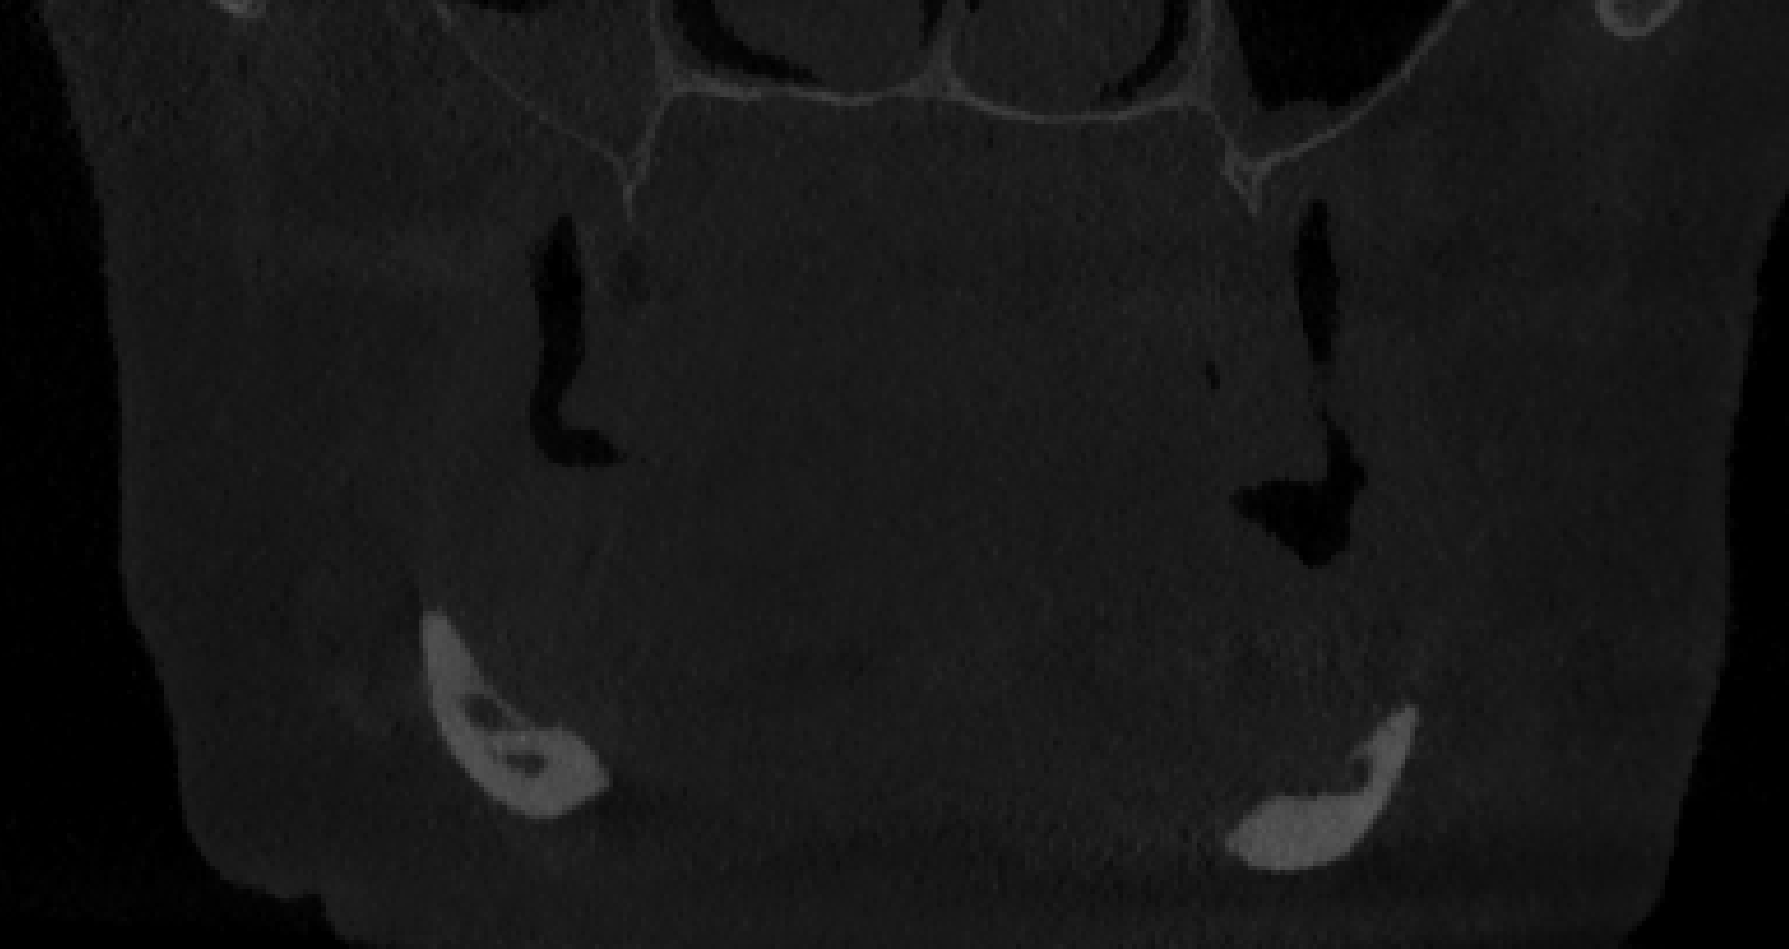

Paziente donna, di razza caucasica, di età 75 anni, edentula totale, che presentava una severa atrofia della mandibola con esposizione completa del nervo alveolare lungo tutto il corpo mandibolare fino al ginocchio dell’emergenza mentoniera (fig. 1a, b) e concomitante atrofia del mascellare di classe VI di C e H. La paziente non presentava patologie avverse al tipo di impianto iuxta scelto. Effettuata una ceratura diagnostica con prova denti mascellari e mandibolari per una corretta progettazione della dimensione verticale, si replicano i risultati mediante stampa 3D in resina con reperi radio-opachi per ottenere 2 dime occlusali da utilizzare durante l’acquisizione dei dati DICOM di una TC Spirale (layer thickness 0.6mm) al fine di costruire un modello osseo tridimensionale della Paziente in posizione ortognatica. Ciò al fine di progettare e produrre la struttura metallica dell’impianto iuxta osseo tripodale (per le ragioni anatomiche precedentemente esposte si è optato per questa soluzione), basandosi sulla posizione dei denti futuri riaccoppiando al dato radiologico dicom le scansioni delle dime stesse (fig. 2).

atrofia della mandibola e nervo scoperto

Fig. 1(a). Vista coronale atrofia mandibola ed esposizione nervo.